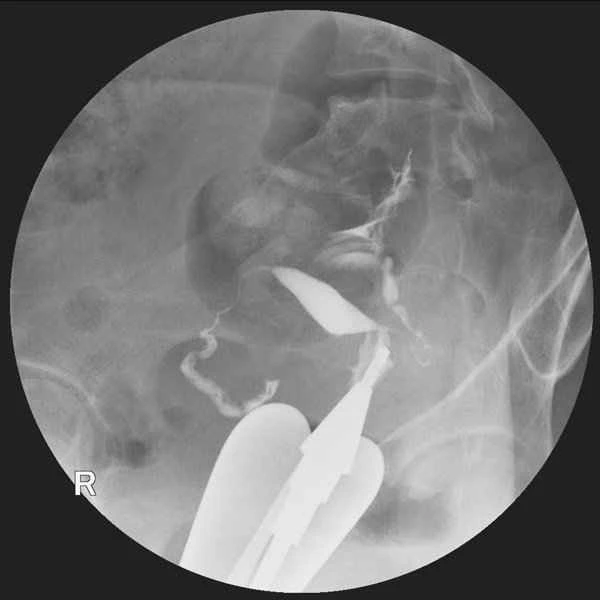

Incomplete intestinal obstruction refers to partial blockage of the intestine, resulting in impeded passage of intestinal contents, but not complete cessation. This condition may not show obvious abnormalities on CT scans because CT images primarily reflect anatomical structures, while the symptoms of intestinal obstruction are more often caused by functional impairments. Weakened intestinal motility, accumulation of gas and fluid in the intestines, and other functional changes may not be directly visible on CT images. Even if the CT scan results are normal, patients may still experience symptoms such as abdominal pain, bloating, nausea, and vomiting. Treatment of incomplete intestinal obstruction typically requires a comprehensive strategy, including fasting, gastrointestinal decompression, fluid and electrolyte replacement, and the use of medications to promote intestinal motility. These measures aim to alleviate symptoms and restore intestinal function. Fasting reduces the burden on the intestines, gastrointestinal decompression relieves bloating, fluid and electrolyte replacement corrects imbalances, and medications to promote intestinal motility help restore normal intestinal function. These measures work together to achieve the therapeutic goal.

In cases of incomplete intestinal obstruction, it is important to recognize that a normal CT scan does not necessarily mean the condition is mild or requires no treatment. Physicians need to comprehensively assess the patient's condition by considering their clinical symptoms, physical examination, and possible auxiliary examination results, such as abdominal X-rays and blood tests. Patients may encounter some treatment challenges, such as medication side effects and malnutrition, which require attention and management during treatment.